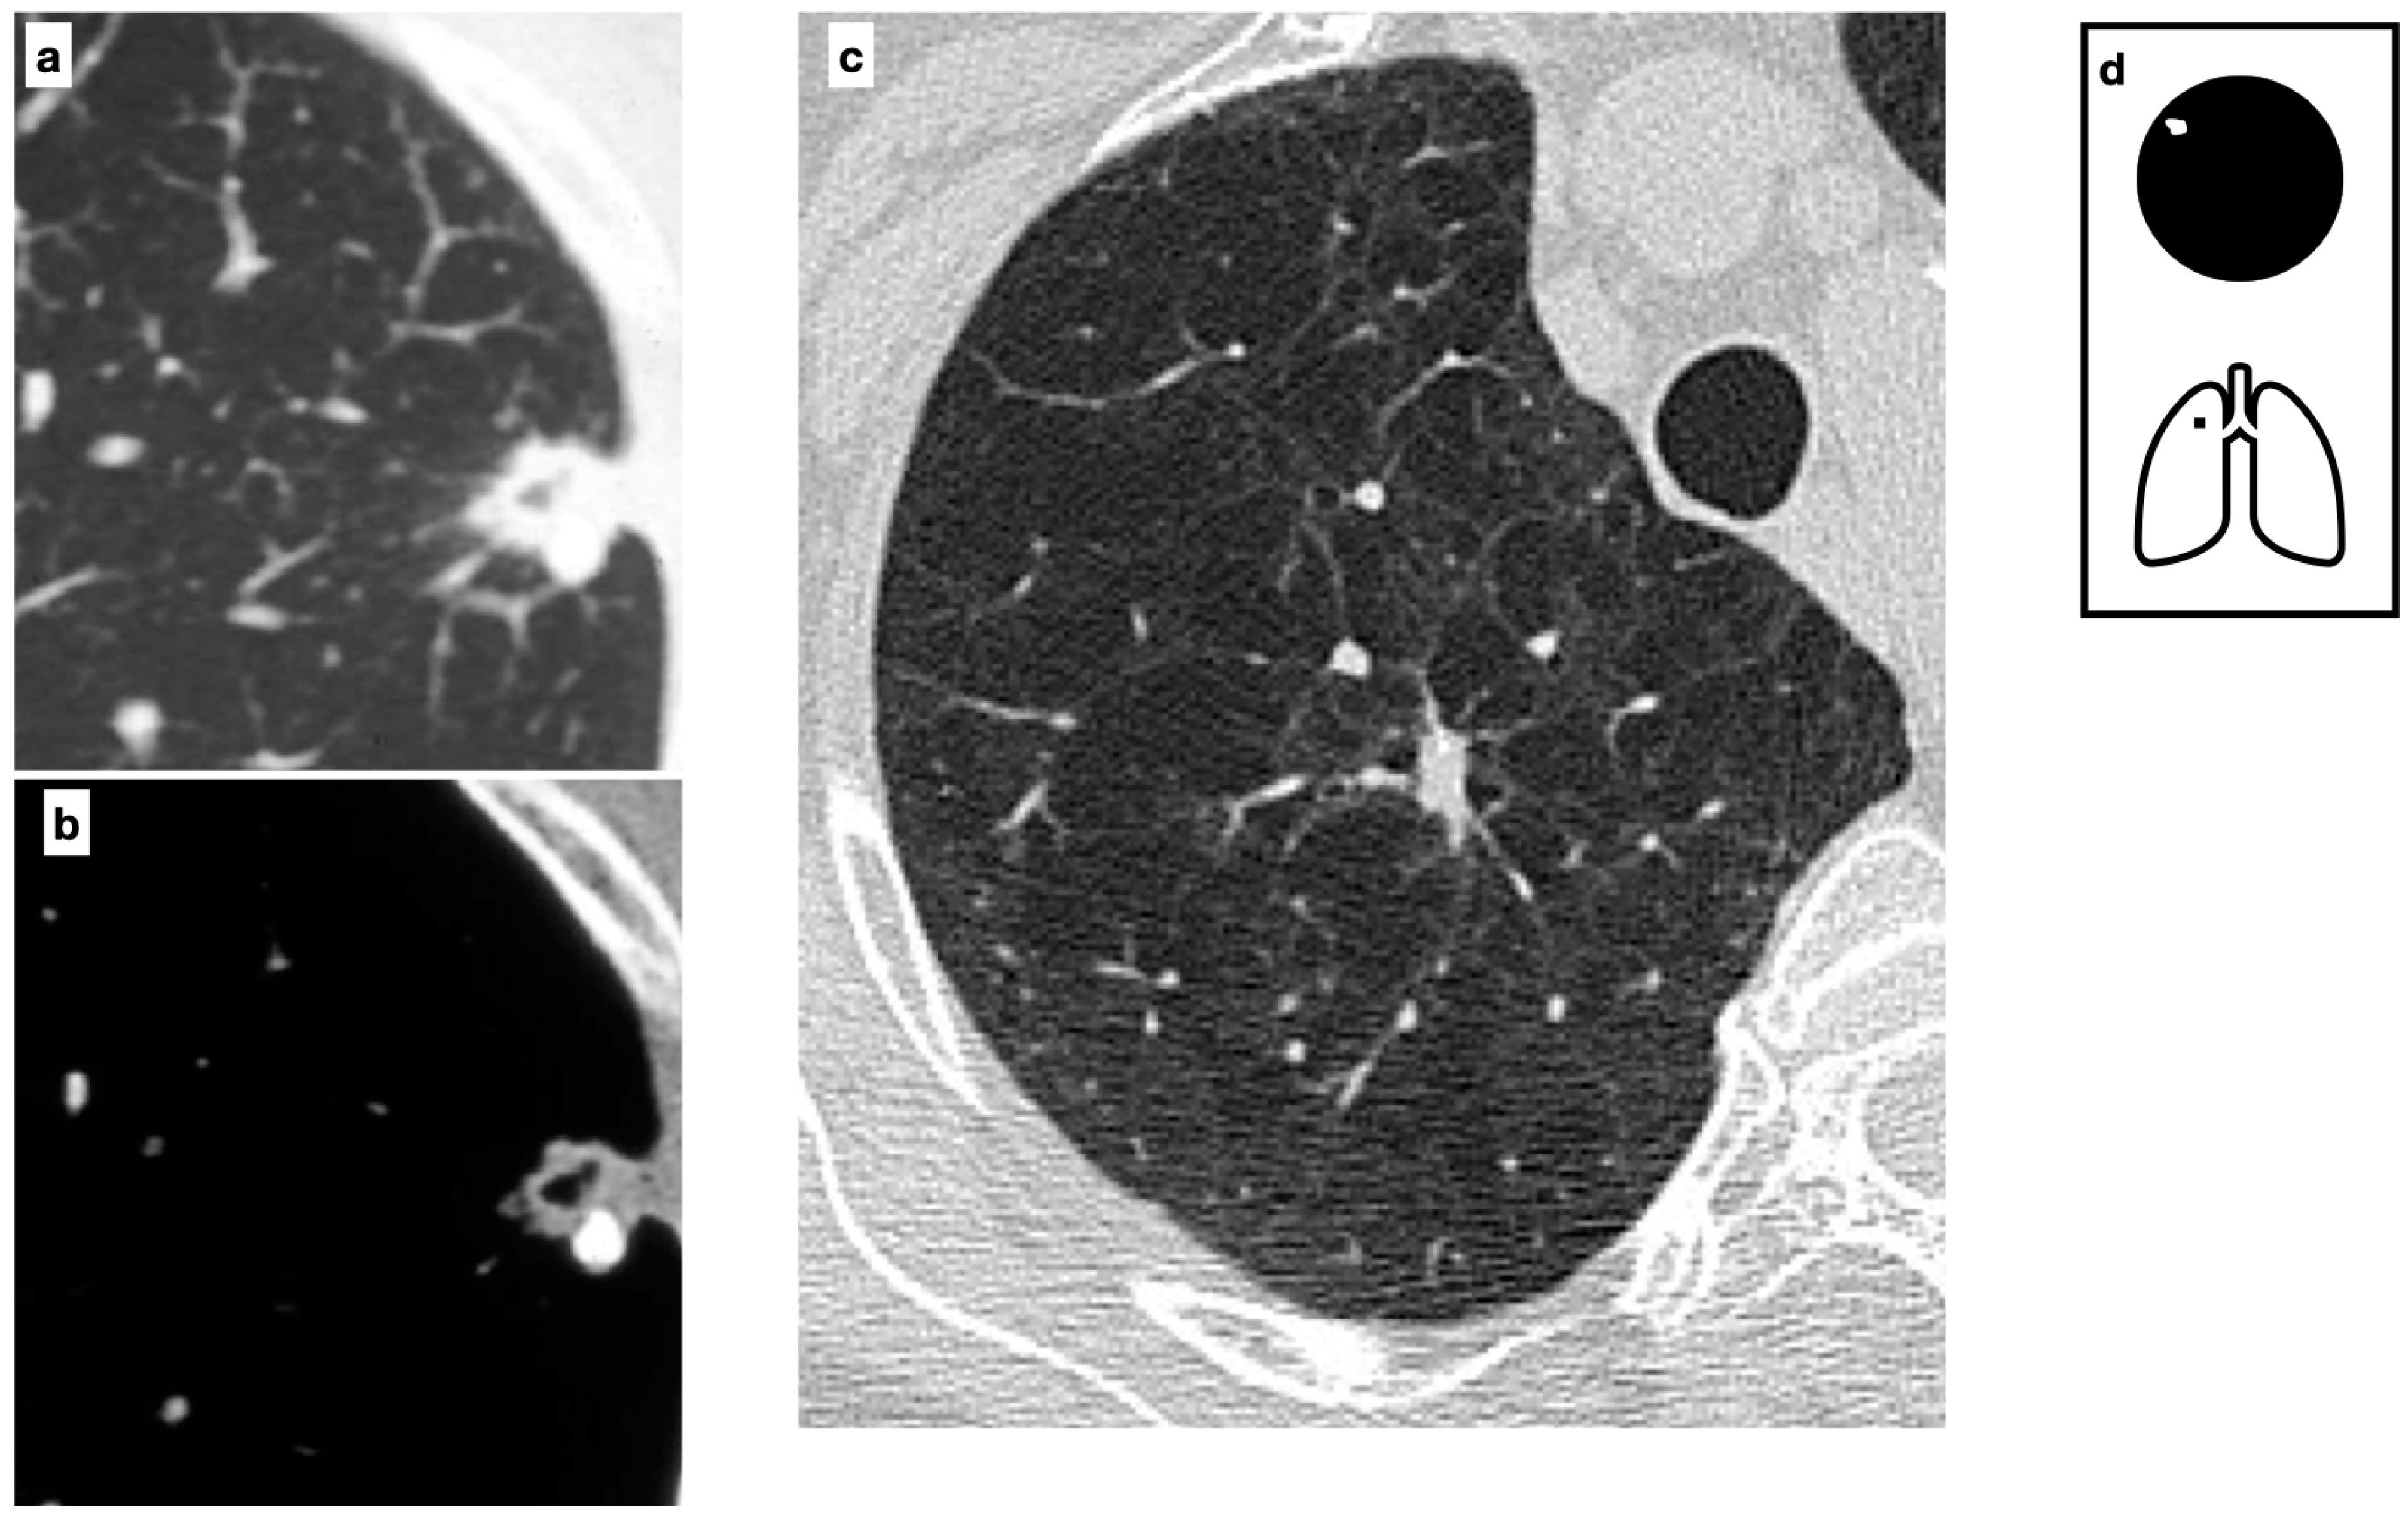

The most common calcification patterns in lung cancer are amorphous or punctuate. However, when a malignant lesion engulfs a pre-existing calcified benign nodule, an eccentric calcification pattern may be seen (Figure 9).

Figure 9.

CT axial images demonstrate a peripheric lung nodule characterized by spiculated margins, small cavitation and an eccentric calcification; this lesion was a biopsy-proven adenocarcinoma (a,b). Heavy smoker patient with severe confluent centrilobular emphysema. HRCT shows a malignant nodule with a small eccentric calcification in the right upper lobe (c). A spiculated nodule with a relatively fast growth rate must always raise the concern for lung cancer in patients with smoking history. Pattern of calcification (d).